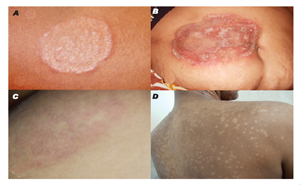

Mycoses Journal: Published on April 2021Dermatomycoses of zoophilic origin,

especially those caused by Trichophyton mentagrophytes, often pose considerable

therapeutic problems. This is reflected in the growing number of strains of

this species with resistance to terbinafine caused by a mutation in the

squalene epoxidase (SQLE) gene. TAKE HOME...